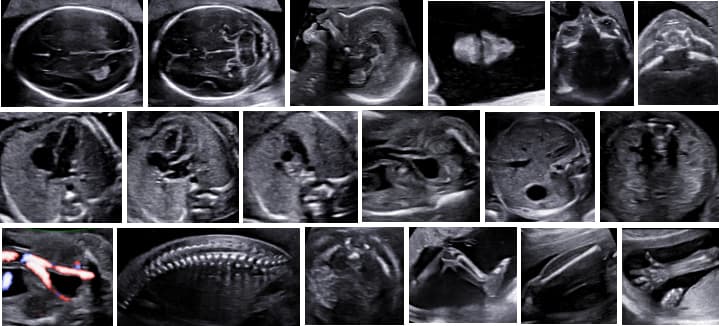

Ukázka správného logbooku snímků UZ vyšetření ve 20.-22. týdnu těhotenství

UZ vyšetření ve 20.-22. týdnu dle FMF protokolu

Podmínky FMF certifikace pro vyšetření UZ vyšetření ve 20.-22. týdnu:

Účast na Světovém kongresu pořádaném FMF a FMF Pokročilého kurzu fetální medicíny (nebo dva teoretické FMF certifikované kurzy u MUDr. Veronika Frisová) Zaslání logbooku snímků z UZ vyšetření jednoho plodu ve 20.-22. týdnu Přezkoušení FMF uznávaným (možno lokálním) školitelem ze znalostí a dovedností týkajících se UZ vyšetření ve 20.-22. týdnu těhotenství

Teoretické FMF certifikované kurzy MUDr. Veroniky Frisové probíhají ve spolupráci s firmou Nimotech 2 x ročně. Praktický kurz s nácvikem dovedností a vysvětlením principů UZ vyšetření ve 20.-22. týdnu těhotenství je možno absolvovat v našem centru u MUDr. Veroniky Frisové, Ph.D. MUDr. Veronika Frisová je uznávanou mezinárodní FMF školitelkou. Na základě kurzů Vám budou vystaveny FMF certifikáty a po splnění podmínek Doporučující dopis pro udělení FMF certifikátu z Londýna. Pro bližší informace neváhejte MUDr. Frisovou kontaktovat.